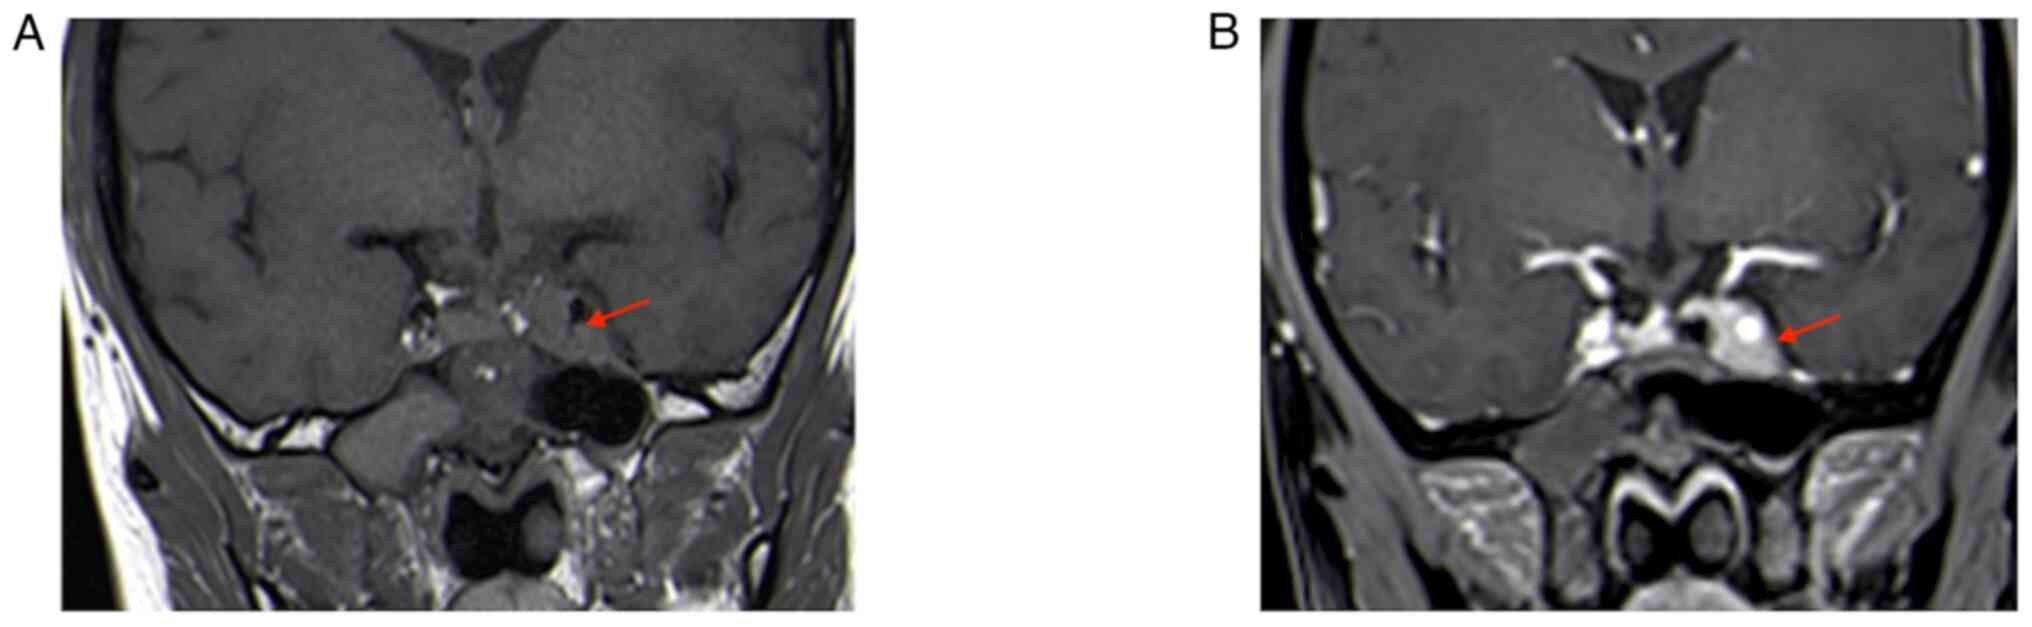

The second MRI (January 2022) performed at the hospital of the present study (the Affiliated Suzhou Hospital of Nanjing Medical University, Suzhou, China) indicated that the tumor grew and was significantly enlarged; it invaded bilateral cavernous sinuses (size, 30×20×18 mm; Fig. 2). Following a thorough evaluation of the patient's condition, a transnasal endoscopic saddle area tumor resection was performed at the hospital of the present study and the tumor was successfully removed. During the operation, the right part of the tumor was soft and could be removed by suction following spatula release; however, the left part was firm and could not be removed by suction; therefore, the tumor was slowly shattered with a curette and removed with tumor removal forceps. The tumor invaded the left cavernous sinus, which was considered to be its origin; bleeding was apparent when the tumor was scraped. Postoperative MRI indicated an extracted cavity with lack of enhancement over the original tumor location, suggesting satisfactory tumor clearance (Fig. 3).

Figure 2.

Review MRI 3 months after the first surgery (January 2022). (A) T2-weighted MRI; (B) enhanced T1-weighted coronal image; lesion size, 30×20×18 mm (red arrows indicate lesion areas); (C) enhanced T1-weighted sagittal image. Red arrows indicate lesion areas.